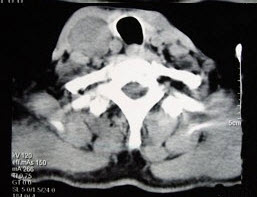

- 多项选择题男性,70岁,右侧颈部无痛性肿块3个月,CT扫描如图所示,请选择正确的描述和答案()。

A、右颈动脉间隙内见类圆形软组织肿块影,密度欠均匀,边缘光整

B、右侧颈静脉被推压至肿块外后方

C、右侧颈动脉被推压至肿块内后方

D、考虑迷走神经源性肿瘤

E、考虑交感神经源性肿瘤

- A,C,D